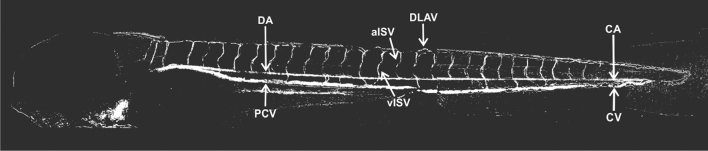

Due to the movement of blood cells, the vascular anatomy of the developing zebrafish embryo can be visualized by subtraction of video frames. Structures in the trunk region can be easily assessed as the region is mostly transparent at 96 hpf (Fig. 1). For the assessment of effects on angiogenesis, we selected 96 hpf given that the development of the cardiovascular system is quite advanced at this stage and various types of structures are visible by video frame subtraction including the caudal aorta (CA), caudal vein (CV), posterior caudal vein (PCV), venous and arterial intersegmental vessels (vISV and aISV), and to a limited extent, dorsal longitudinal anastomotic vessels (DLAVs). Vascular structures located in the trunk at this stage are difficult to analyze by the image subtraction approach due to shading by pigmentation. Qualitative inspection of all subtraction images indicated that vascular structures (DA, CA, PCV and CV) were not affected in any of the treatments. Therefore, and given that the focus of the work was on angiogenesis, we investigated ISVs in all subsequent analyses.

Fig. 1.

Angiogram obtained by video frame subtraction of a zebrafish embryo at 96 hpf, compiled from nine separate and overlapping images obtained with a 20 × objective. DA—dorsal aorta, PCV—posterior cardinal vein, aISV—arterial intersegmental vessel, vISV—venous intersegmental blood vessel, DLAV—dorsal longitudinal anastomotic vessel, CA—caudal artery, CV—caudal vein